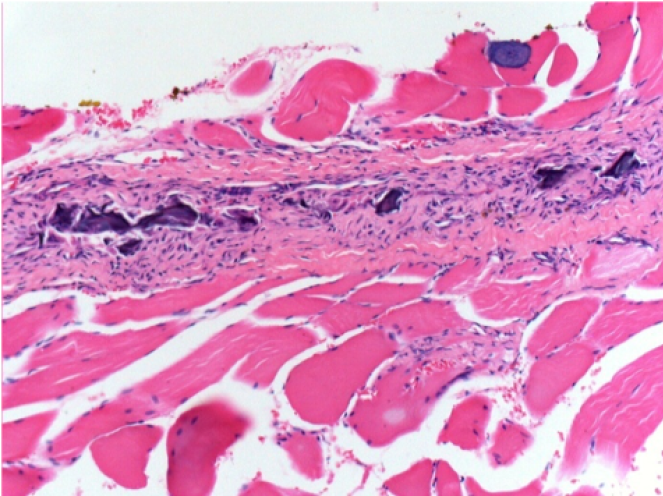

Через 1 місяць після ін'єкції Ендопілу 0,1 мл у правий претибіальний м'яз.

Те, що видно на знімках чорним кольором, не є некрозом, як можуть собі уявити деякі науковці!

Насправді, слід взяти до уваги 4 висновки